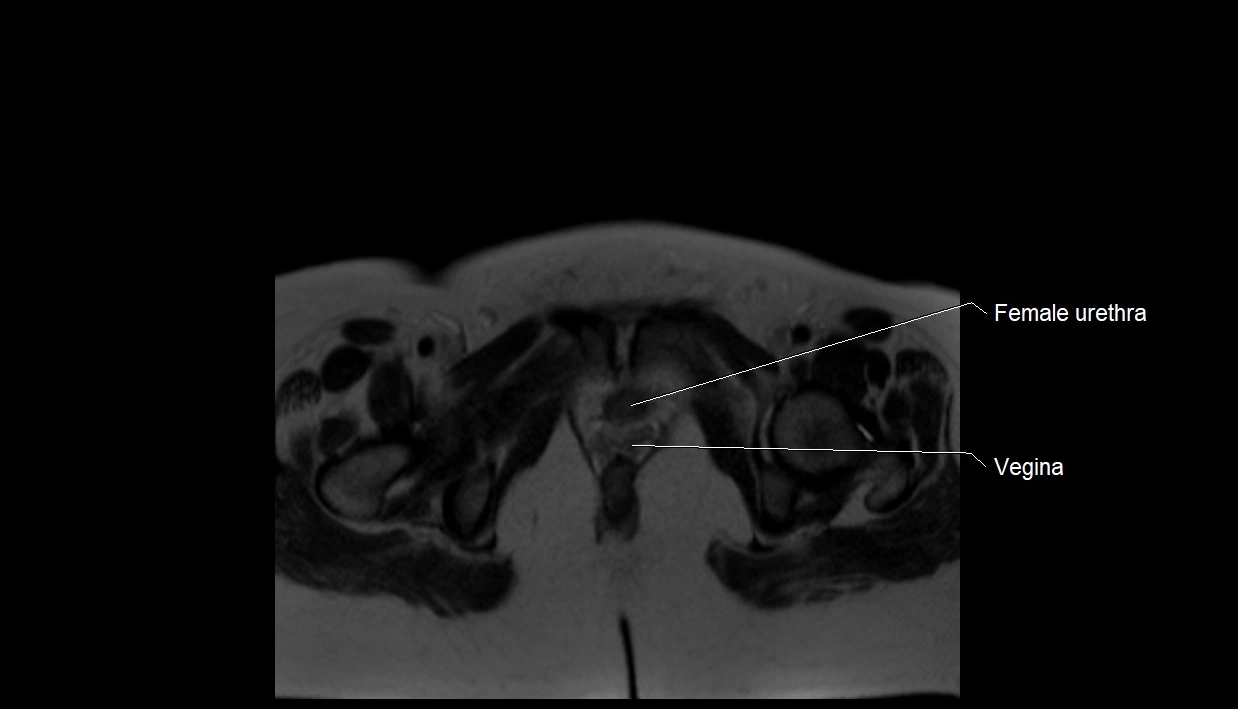

MRI Appearance

T2 HASTE (T2 GRE):

• Amniotic fluid shows very bright hyperintense signal

• Provides natural contrast against fetus and placenta

• Small particles (vernix) may appear as scattered hypointense foci within bright fluid

T1 GRE:

• Amniotic fluid shows low signal intensity (dark)

• Hemorrhage, infection, or proteinaceous content may cause focal or diffuse high signal intensity